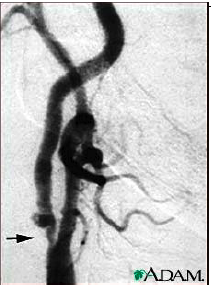

*Compare to “gold standard” angiogram - complex (maps out vascular tree incl circle of willis for surgeon)

what does the Bluth Criteria or Bulb Method Angio demonstrate?

Percent stenosis based on residual lumen and true lumen at the same location

*anytime we are talking about % stenosis, the info is compared to a gold standard. meaning the exam we use is the “closest to truth”. in vasc, angiography is still considered the gold standard.

*stenosis is estimated by the % of remaining lumen

US - u can see vessel wall, angio you can’t. so they can underestimate in angio b/c they cannot see how wide the bessel is supposed to be as they can only see flow not vessel walls.

Comparison of angiogram measure methods

what does NASCET compare to ?

distal ICA

Angio NASCET method may underestimate stenosis compared to US 2D method (b/c bulb is bigger than distal ICA)